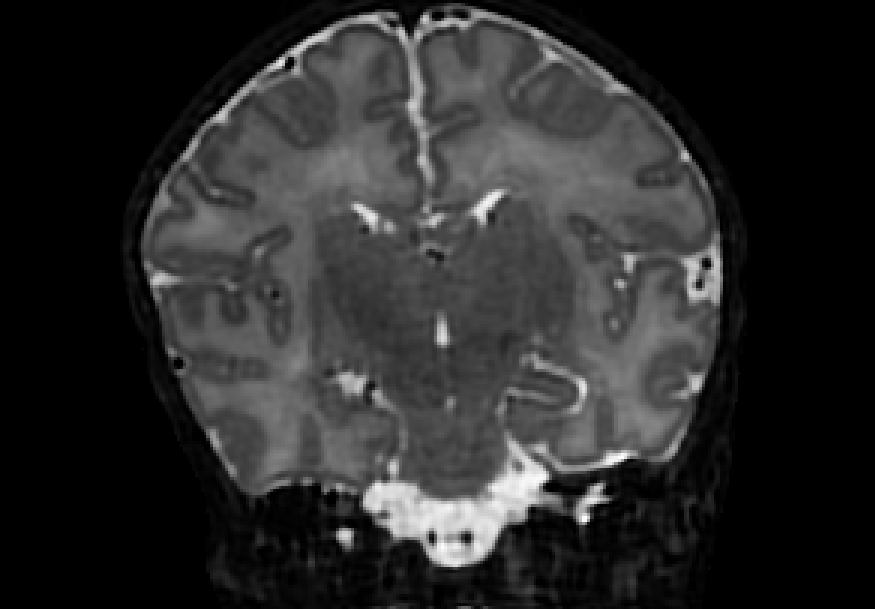

The dataset consisted of 70 3D T2-weighted brain MRI scans publicly available from the dHCP neonatal cohort. The segmentation maps had 10 classes, corresponding to: zero-pixel background, cerebrospinal fluid (CSF), cortical grey matter (cGM), white matter (WM), background bordering brain tissues, ventricles, cerebellum, deep grey matter (dGM), brainstem, and hippocampus. The scans covered an age range of 24.3-42.2 weeks. The data was available in NIfTI format; Figure 1 shows an example scan and corresponding tissue labels. We carried out a pre-processing step where each scan was independently normalised to zero-mean and unit-variance.